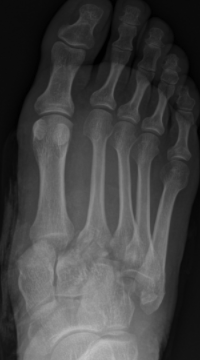

This is an AP View of the Right foot

AP view of a radiographic image of a right foot showing the lateral dislocation of metatarsal bases 1-5. A diastasis is noted at the base of the 1st and 2nd metatarsal bases, and a nondisplaced transverse fracture at the base of the 2nd metatarsal. These findings are consistent with a homolateral Lisfranc dislocation. A chip fracture is noted from the cuboid laterally.